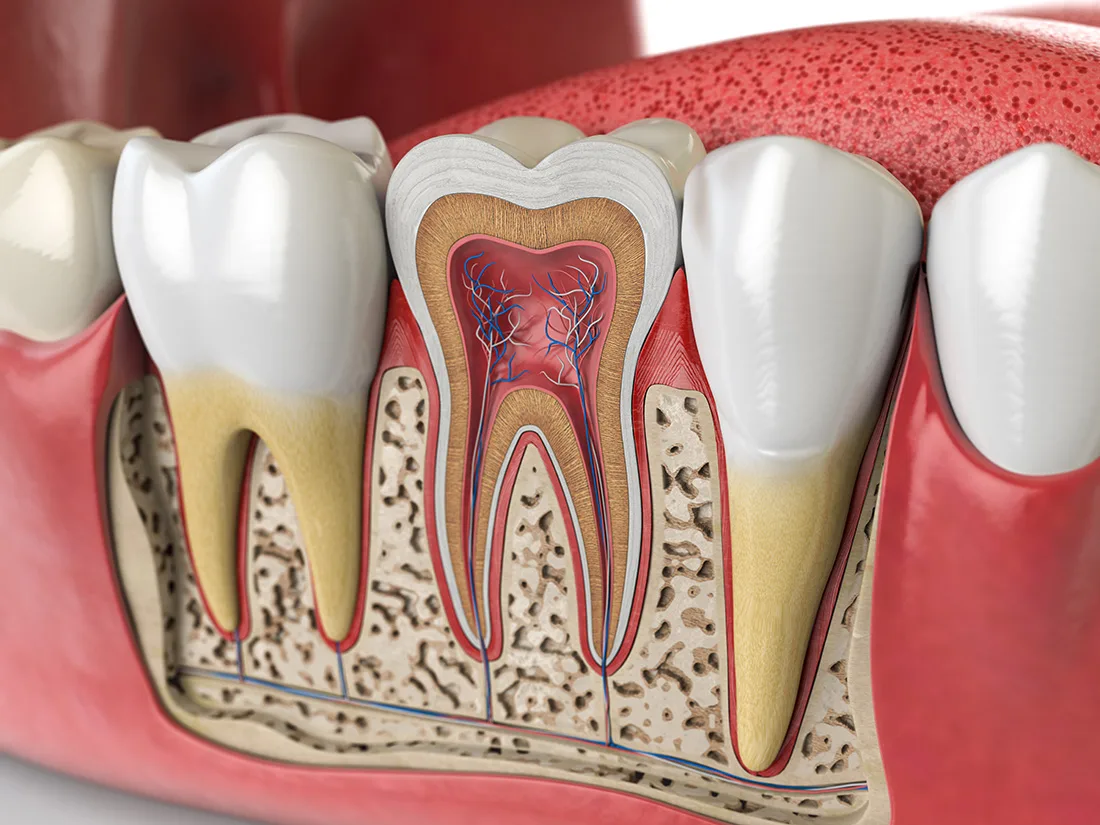

Once you're fully numbed and comfortable, your dentist will begin the process of removing decayed or infected material. They'll start from the outermost layer of enamel and work their way towards the inner pulp. After removing the infected pulp, the canals will be thoroughly cleaned and flushed with a specialized disinfectant to eliminate any remaining infection.

After cleaning and disinfecting your tooth, your dentist will fill the inner cavity with a rubbery substance called "gutta-percha". This inert material provides support to the tooth and replaces the extracted pulp. Following this, your dentist will determine whether to restore the tooth with a filling or a dental crown. This decision is based on the extent of decay and the amount of healthy enamel remaining on the tooth.